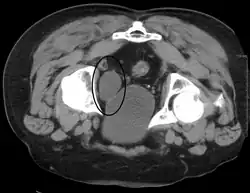

Investigations performed usually include collecting a sample of urine for an inspection for malignant cells under a microscope, called cytology, as well as medical imaging by a CT urogram or ultrasound.[33] If a concerning lesion is seen, a flexible camera may be inserted into the bladder, called cystoscopy, in order to view the lesion and take a biopsy, and a CT scan will be performed of other body parts (a CT scan of the chest, abdomen and pelvis) to look for additional metastatic lesions.[33]

Some forms of medical imaging exist to visualise the bladder. A bladder ultrasound may be conducted to view how much urine is within the bladder, indicating urinary retention. A urinary tract ultrasound, conducted by a more trained operator, may be conducted to view whether there are stones, tumours or sites of obstruction within the bladder and urinary tract. A CT scan may also be ordered.

A flexible internal camera, called a cystoscope, can be inserted to view the internal appearance of the bladder and take a biopsy if required.